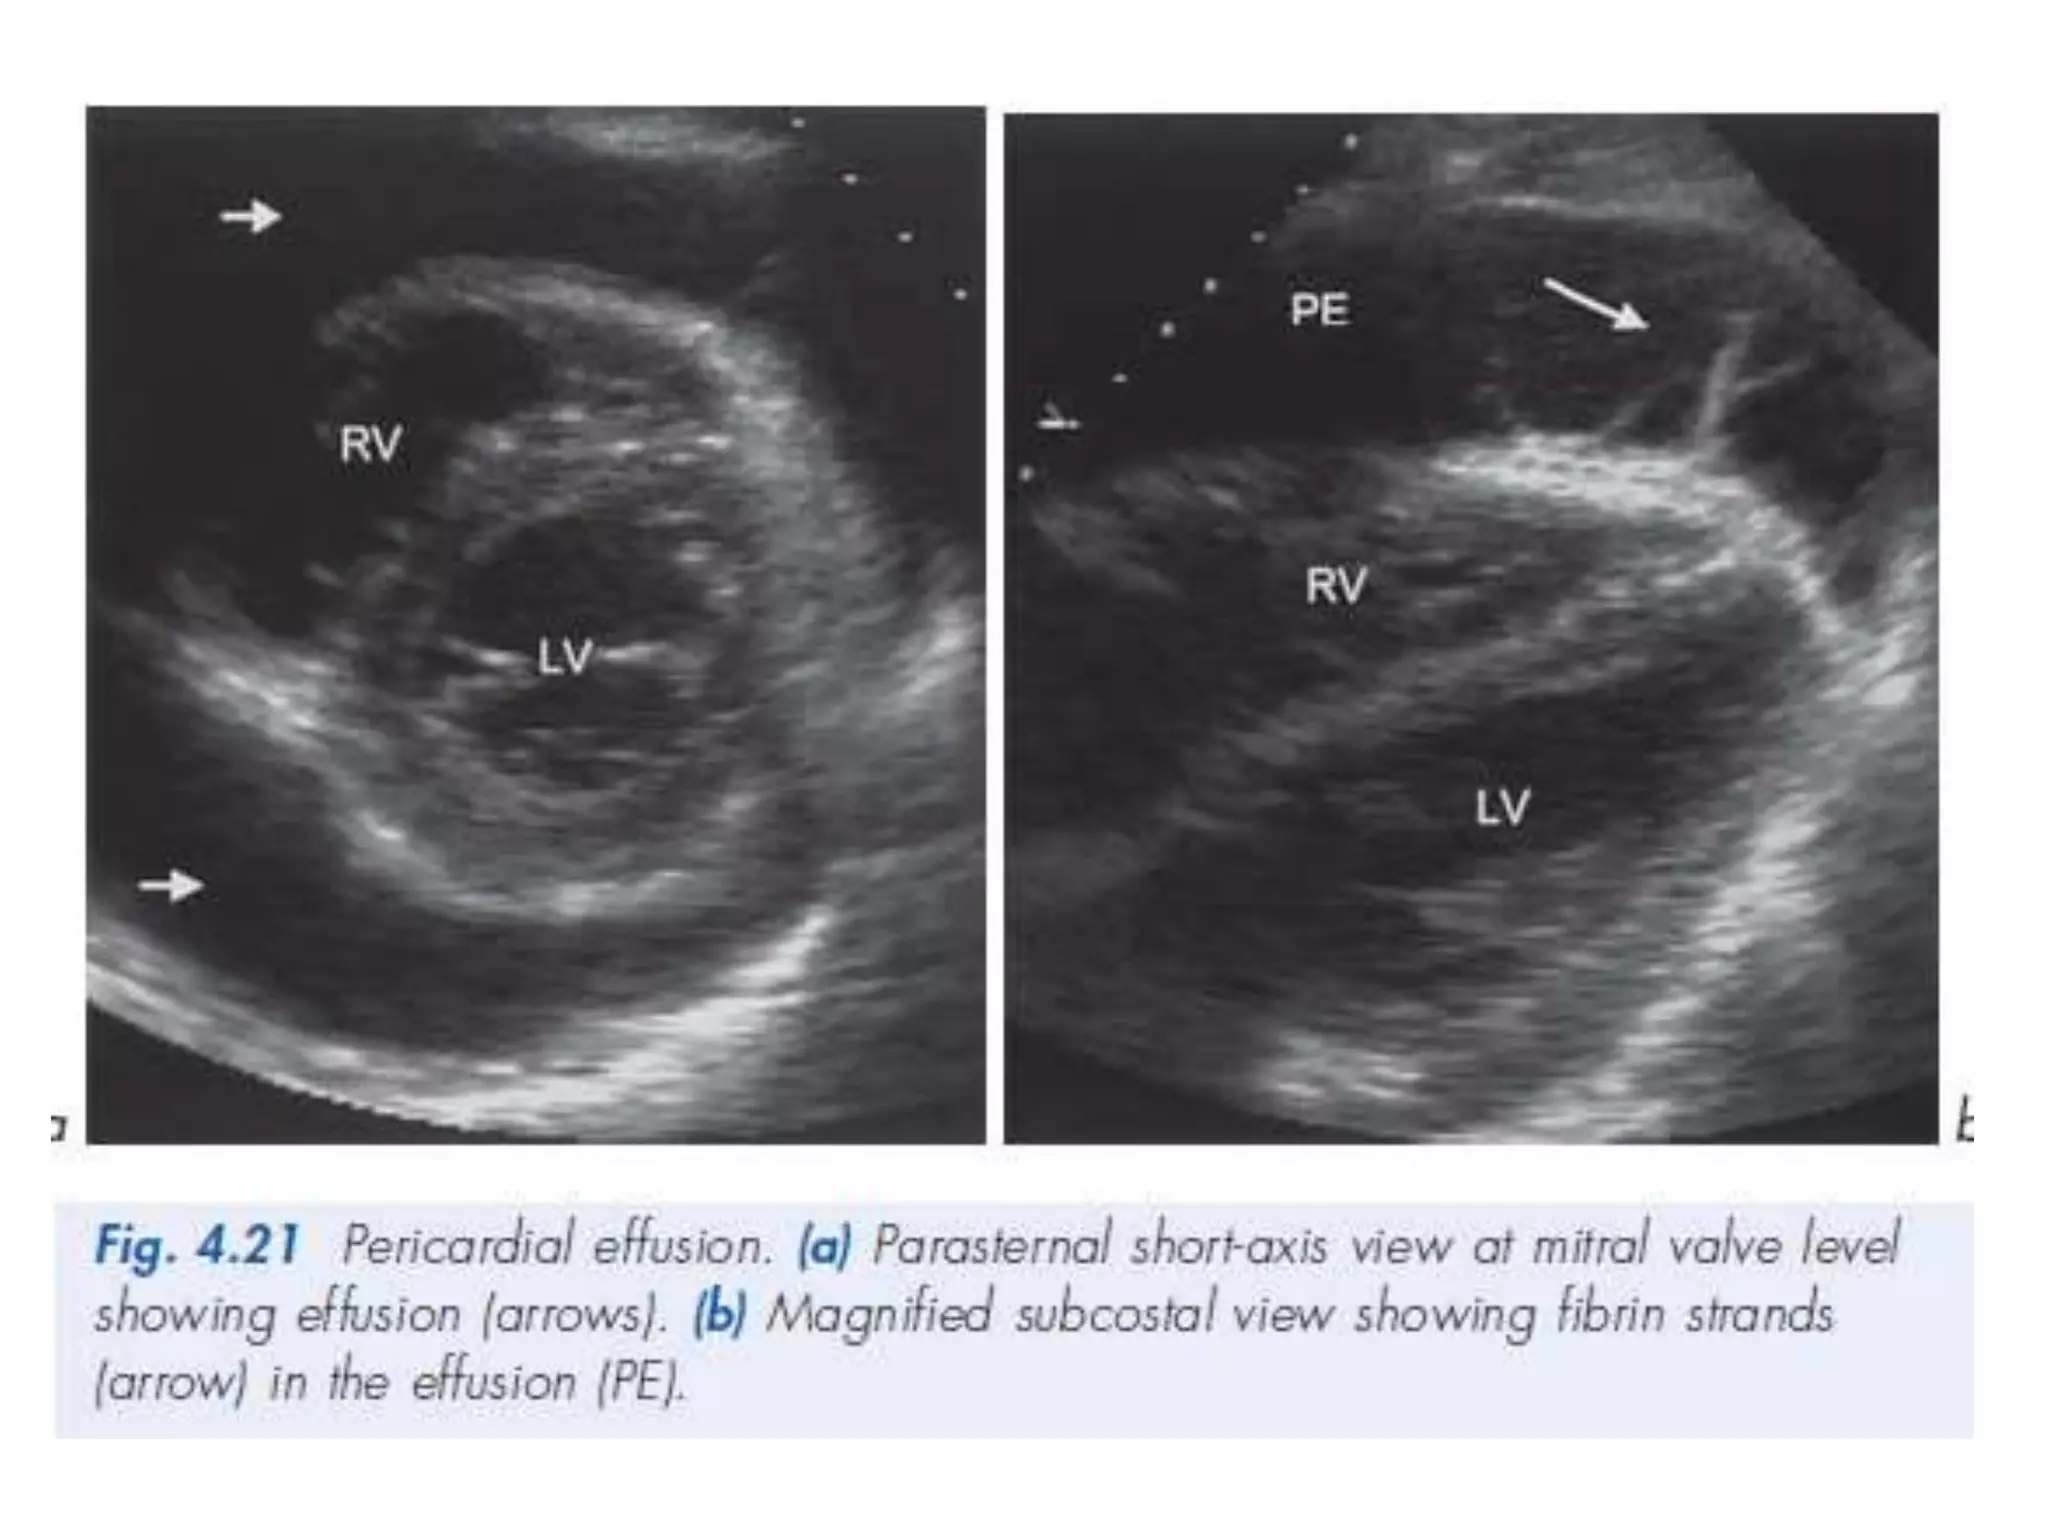

PERICARDIAL EFFUSION